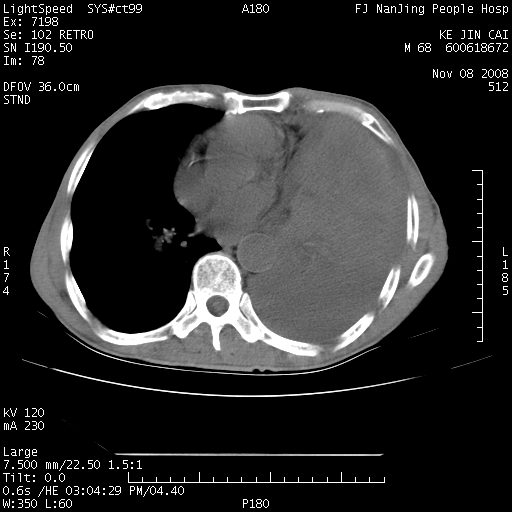

是个很有看头的病例,咋人气那么不旺?没多少人兴趣呢?这个病例几大怪:1   恶性肿瘤侵犯心肌左房怪,心肌一般不会被恶性肿瘤侵犯吧?2   左下肺均匀实变怪,内无含气,有别一般不张实变,含气肺泡完全为液体取代,而非一般不张实变的肺萎陷,冷不丁还以为是肿大的脾脏3   肿瘤本身怪,像tb肺不张4   这么有看头的病例没人气怪。呵呵。

追查病史,咳嗽,患者无发热,血象不高。据说2年前胸片检查怀疑肺ca曾行纤支镜检查,病理未见到癌细胞。无确切资料。

左肺恶性肿瘤侵犯肺动脉,左心房内瘤栓,胸膜转移。